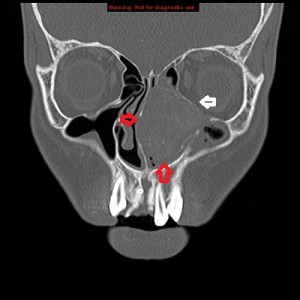

First panel, left to right: Axial contrast-enhanced maxillofacial CT scan in soft-tissue window from superior to inferior, showing a large, avidly enhancing mass in the left nasal fossa, extending posteriorly into the left nasopharnx and crossing into the right nasopharynx behind the nasal septum. Note opacification of the right and left maxillary sinuses, possibly from disturbed drainage.

Third panel, left to right: The first 2 images are coronal sections of the face showing the mass-effect of the left nasal mass on other surrounding structure.The third image in this panel is a sagittal paramedian section showing obstruction of the nasopharynx by a soft-tissue mass.